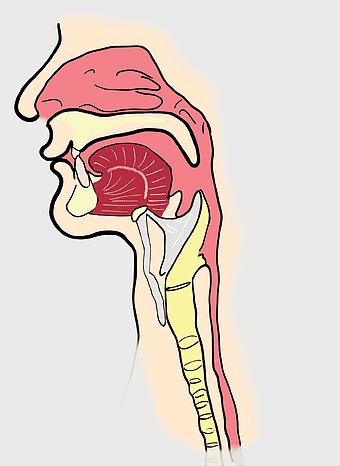

Pulmonary edema symptoms, chronic obstructive pulmonary disease diagram, kidney failure effects on lungs, pulmonary circulation illustration, lung disease diagnostic, respiratory health visuals, human anatomy respiratory system, PNG

- pulmonary edema symptoms

- chronic obstructive pulmonary disease diagram

- kidney failure effects on lungs

- pulmonary circulation illustration

- lung disease diagnostic

- respiratory health visuals

- human anatomy respiratory system

Pharynx anatomy, Otorhinolaryngology diagram, Throat larynx illustration, Sinus infection symptoms, Respiratory system, Head and neck medical, Upper airway structure -